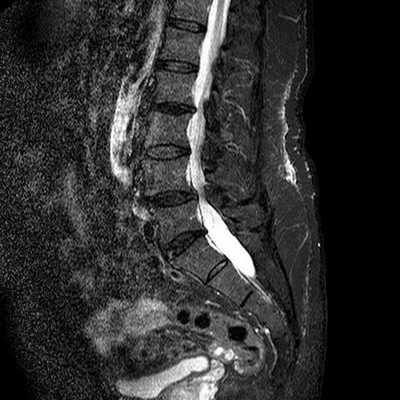

Хордома крестца. Сагиттальные Т1- и Т2-зависимые МРТ.